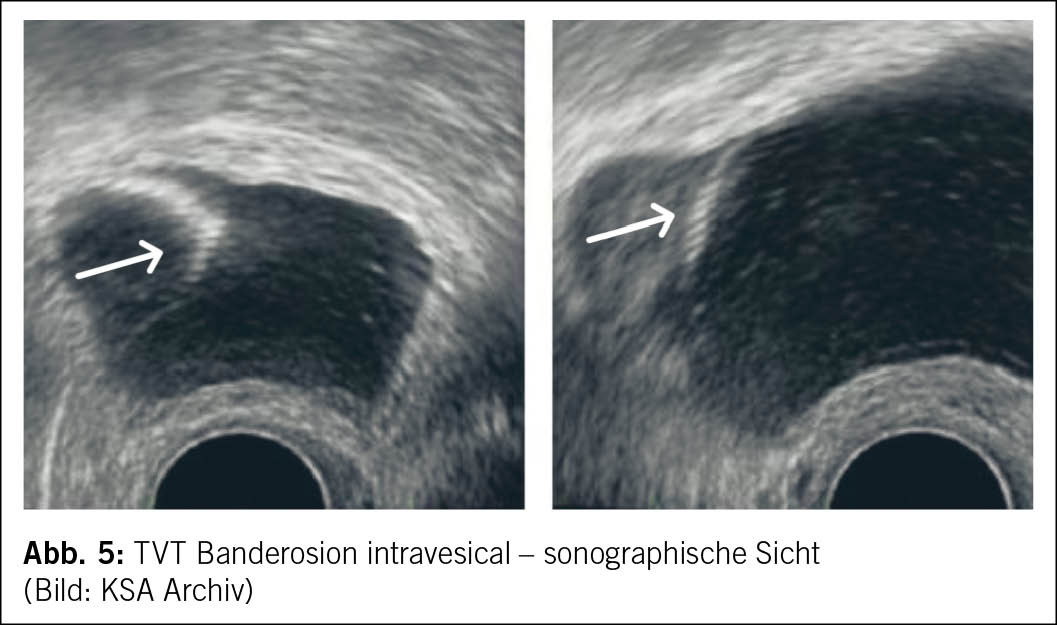

Eine innovative Behandlungsoption für eine nicht erkannte intravesikale TVT-Banderosion stellt der minimalinvasive kombinierte transurethrale und suprapubische Zugang dar. Hierbei werden zwei 3 mm Trokare suprapubisch in die gefüllte Blase eingeführt, um das Band unter Spannung zu halten, während die Resektion des Bands transurethral mittels Zystoskop erfolgt (5) (Abb. 5 und Abb. 6).